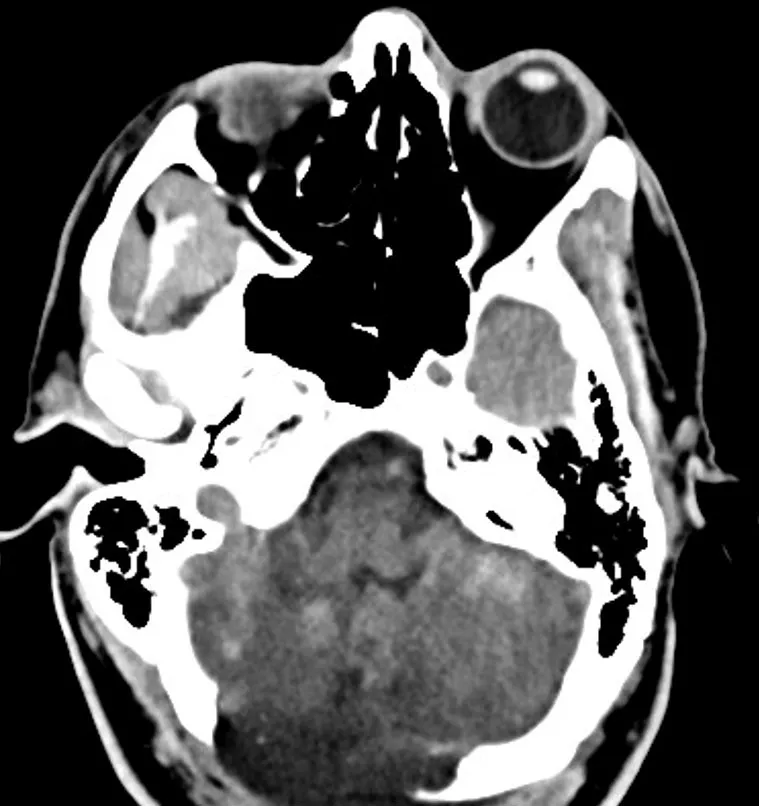

Approximately 12 hours after admission, the patient experienced a decline in his mental status, prompting a stat non-contrast computed tomography (CT) of the head which revealed bilateral cerebellar strokes. The associated cytotoxic edema resulted in significant mass effect on the 4th ventricle and early hydrocephalus.

The patient was then taken to surgery for an emergency sub-occipital decompressive craniotomy and placement of an extra ventricular drain to relieve the pressure.